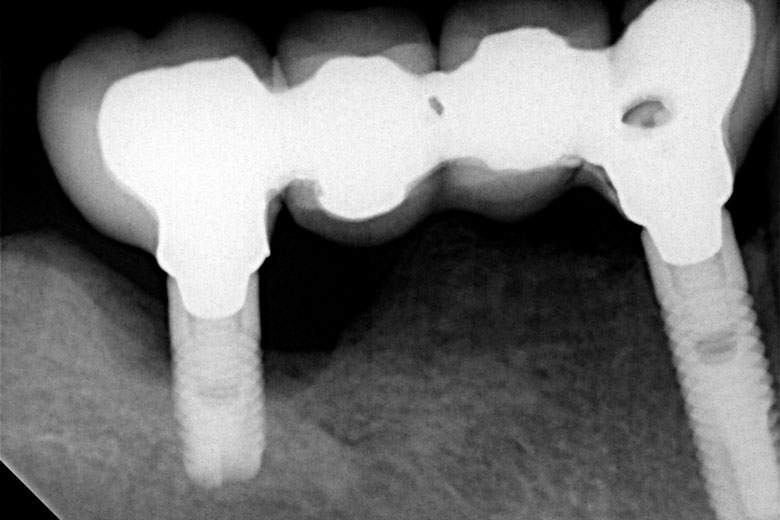

Αποκατάσταση έλλειψης ομάδος δοντιών

Όταν σε κάποια περιοχή του στόματος λείπουν τρία διπλανά δόντια, τότε τοποθετούμε δύο εμφυτεύματα και κατασκευάζουμε μεταξύ τους γέφυρα. Όσο αυξάνει ο αριθμός των ελλειπόντων δοντιών, τόσο μειώνεται η αντιστοιχία δοντιών-εμφυτευμάτων, π.χ. για την αντικατάσταση τεσσάρων ή και πέντε δοντιών συνήθως απαιτούνται τρία εμφυτεύματα.